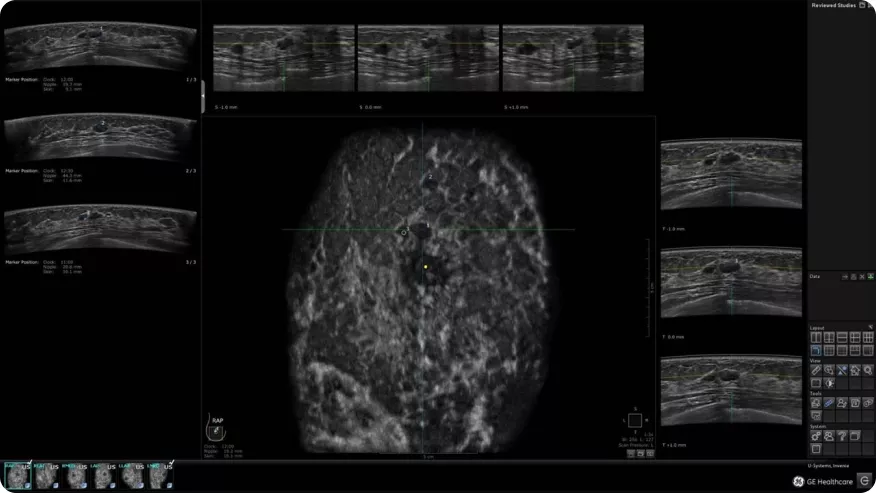

Image

ABUS

ABUS — это система автоматизации и унификации методики УЗИ молочной железы. Унификация позволяет получать трёхмерные стандартизированные изображения определенных областей молочной железы, независимо от опыта и квалификации врача.